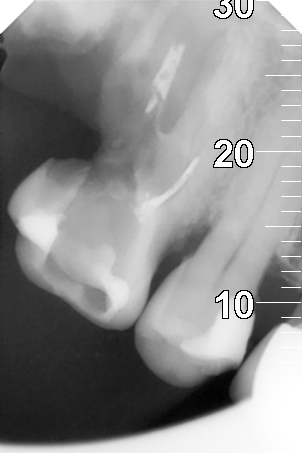

Уважаемые стоматологи!

Какие есть варианты лечения такого зуба?

Нажмите на изображение для увеличения

Название: Зуб6.jpg

Просмотров: 37

Размер:	52.5 Кб

ID:	13574616

Этот 16 зубик лечил не только талантливый дохтУр,но и находился во рту не менее заботливого хозяина. У зубика незавидная судьба. Кстати-и остатки 17 ждет тоже самое.

Цитата Сообщение от Lie Посмотреть сообщение

Увы, только удаление.